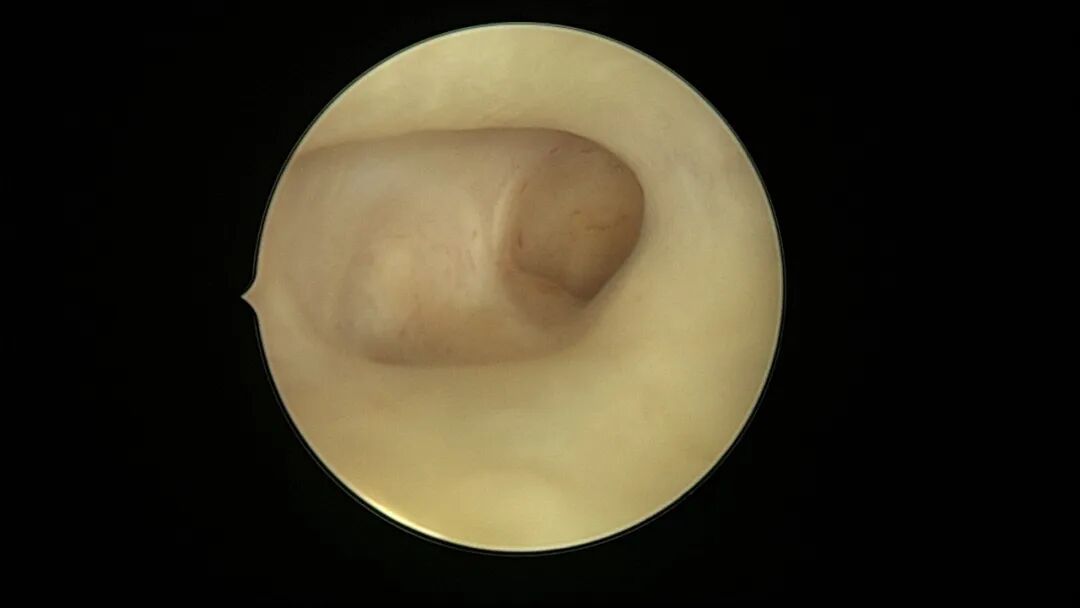

第一次宫腔镜:2021年4月,闭经50+天,B超提示宫腔粘连,宫腔镜探查见宫颈管上段封闭粘连,宫腔广泛粘连,AFS评12分(最高分)。宫腔镜单极电切分粘,恢复宫腔形态,显露双侧输卵管开口,右侧宫角附近内膜柔软、红润,宫腔防粘连复发处理。